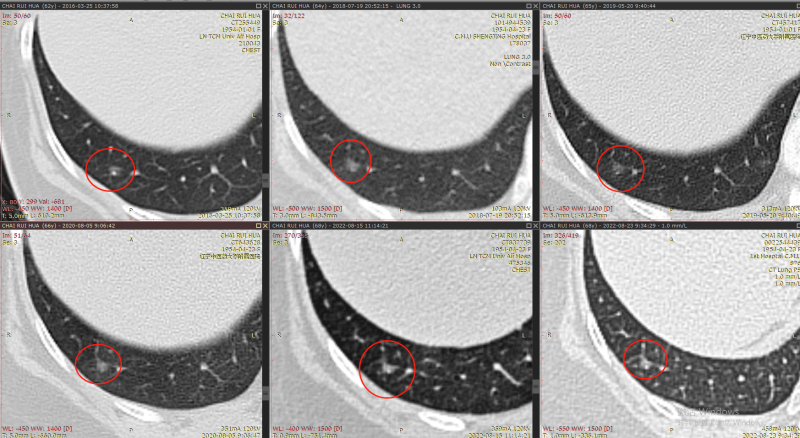

这个结节诊断还是有难度的↓

结节2

2013年↓

诊断:这个结节是一个混杂密度结节,大部分以实性成分为主,周边可见毛刺及分析,由于病灶非常小,如果首次发现还是要小心,但是通过以下多次的随访和复查,我们考虑良性纤维灶的概率更高。

但是由于这个结节位于外周带,非常容易切除,因为和主病灶是同侧,所以这个结节,我么可以考虑一次处理掉。

其余结节:

本次阅片我们用了2个多小时进行了比较:其余结节通过9年的比较,均未见明显高风险,手术可以不用处理。